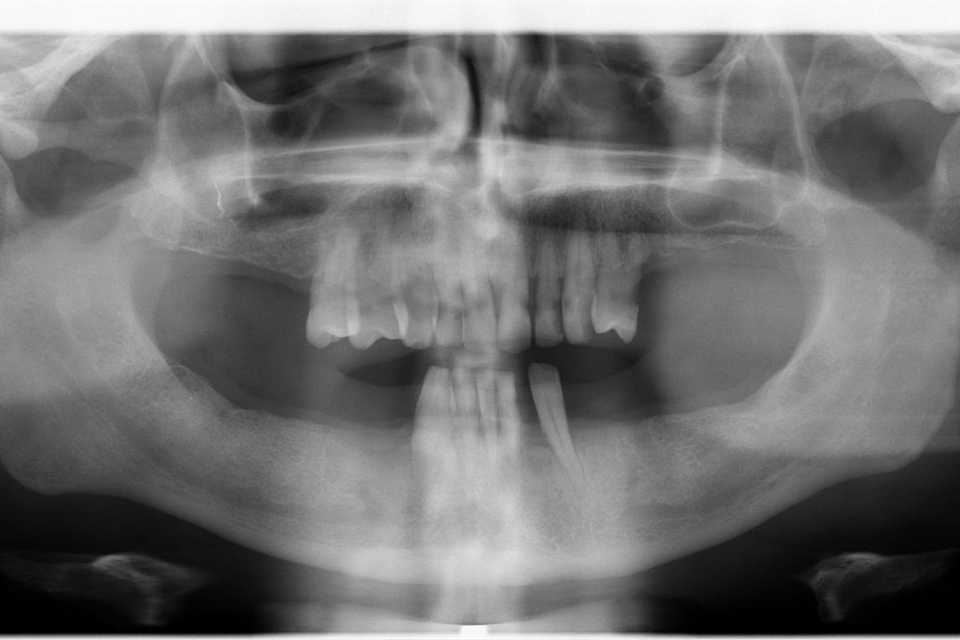

Pacientul, în vârstă de 51 de ani, se prezintă în clinica noastră acuzând tulburări funcționale, dureri la nivelul mandibulei, precum și dorința de a îmbunătăți aspectul estetic.

Prima etapă – sub anestezie loco-regională, s-au efectuat extracția dinților parodontotici, chiuretajul și regularizarea crestei osoase, urmate de inserarea a 6 implanturi dentare Paltop (SUA) (preț: 2.500 lei per implant) și realizarea unei lucrări provizorii din acrilat.

A doua etapă – la aproximativ 5 săptămâni de la prima intervenție, implanturile sunt protezate printr-o lucrare fixă, înșurubabilă, din ceramică pe suport de zirconiu (preț: 1.500 lei per element).